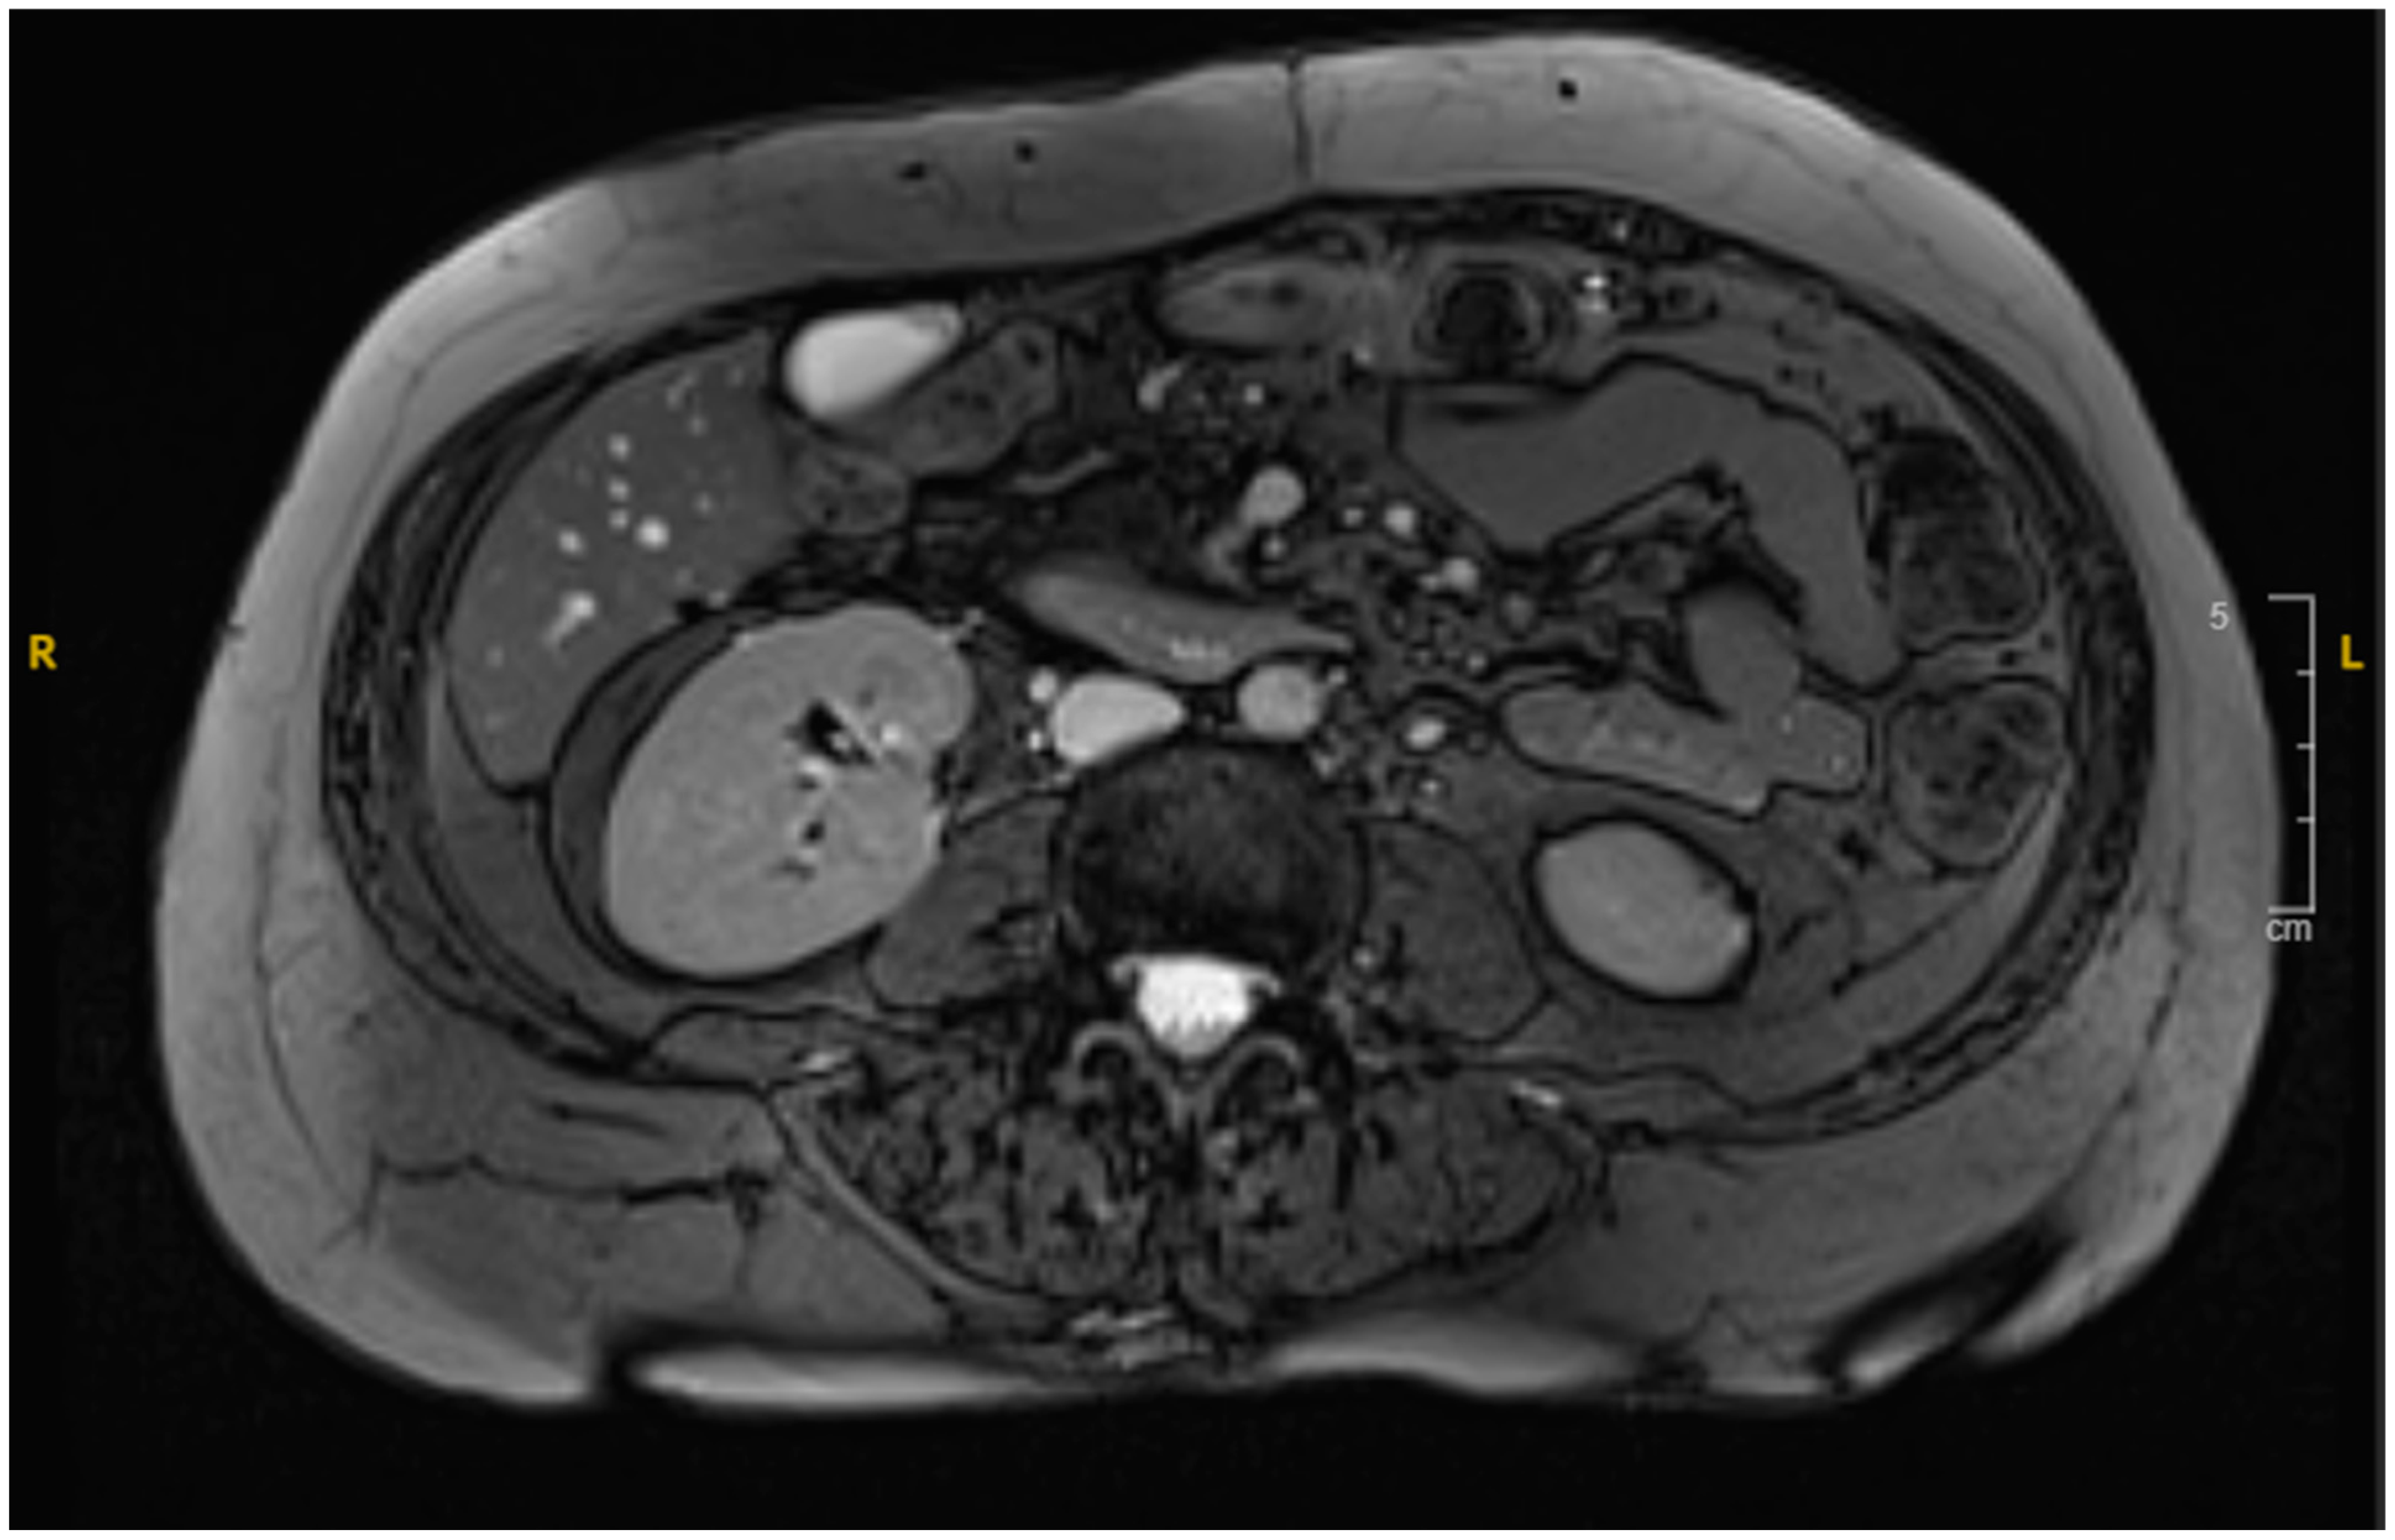

Over the following days, the NG tube suction output remained significant (1–1.5 L daily), and the liver function tests (LFTs) showed a slow uptrend with mixed hepatocellular and cholestatic pattern, likely due to extrinsic compression on the distal common bile duct from the duodenal hematoma. NJ feeding continued, with close monitoring of NG suction output. The patient tolerated the NJ feeds well, and the LFT showed slight improvement. A repeated MRI revealed a reduction in the hematoma size (from 7.8 cm × 5.8 cm to 6.2 cm × 2.5 cm as shown in Figure 3), along with decreased duodenal wall thickness and hyperenhancement. A follow-up EGD revealed improved non-bleeding gastric ulcer and successful passage of the scope through the second portion of the stenosed duodenum.

Figure 3. MRI cholangiogram revealing interval decrease in size of the duodenal hematoma to 6.2 cm in its widest diameter.